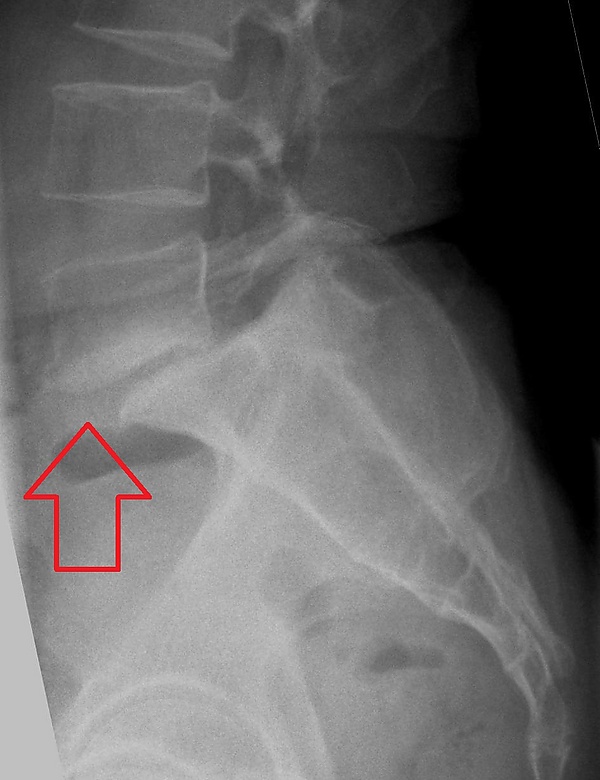

Степень соскальзывания

Боковая рентгенограмма покажет степень смещения позвонка к нижележащему:

• Степень I — смещение до 25 %.

• Степень II — смещение от 26 % до 50 %.

• Степень III — смещение от 51 % до 75 %.

• Степень IV — смещение от 76 % до 100 %.

• Степень V развивается, когда позвонок полностью отделяется от соседнего позвонка (спондилоптоз).